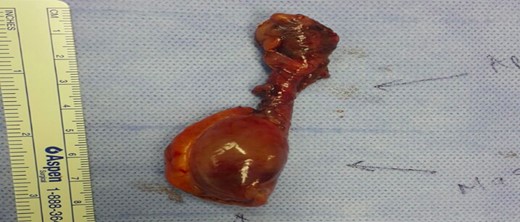

A week later, the patient was seen in the general surgery clinic, still complaining of abdominal pain. CT abdomen was repeated and showed the same findings. A decision was made to admit the patient with a possible diagnosis of an appendicular mucocele or less likely an appendicular carcinoid. A diagnostic laparoscopy with appendectomy and possible right hemi-colectomy was scheduled. Intra-operatively, the appendix was para-caecal and adherent to the caecum with a 3 cm cystic swelling of proximal appendix (Fig. 2). The caecum and ileum were normal and there were no peritoneal deposits. We managed to perform the appendectomy with an intact cystic mass.

Histological examination showed an appendix measuring 7 cm in length and 0.8 cm in diameter with a cystic lesion at the base measuring 3.5 × 2.5 cm2. It had a grey homogenous cut surface invading the appendix wall while the mucosa was unremarkable. The mucosal lining showed elongated and dilated tubules with Goblet cell proliferation with no evidence of dysplasia. The sub-mucosa displayed an area of extensive edema, vascular congestion with focal hemorrhage and abundance of spindle cells, dispersed in a loose fibromyxoid stroma. The sub-mucosal background had copious eosinophils, lymphocytes and blood cells. There was no mitosis, acute inflammation, granuloma, ischemia or vasculitis (Figs 3–6). These findings are consistent with an appendicular IFP (Vanek’s tumor).

The tip and the middle part of the appendix with no specific pathology (H&E stain, low power).

The base of the appendix with the mass (H&E stain, low power).